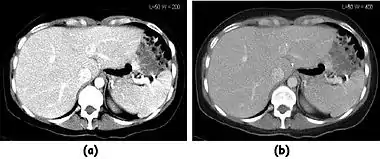

![]() Fig. 7.15.2: Effect of window width and level on CT image display: (a) Level = 50; Width = 200. (b) Level = 50; Width = 400. The image in (a) is displayed with greater contrast and appears noisier than that in (b). | ![]() Fig. 7.15.3: Effect of window width and level: (a) Level = -600; Width = 1700. (b) Level = -60; Width = 400. Image (a) displays the lung tissue more clearly, while image (b) can be used to highlight any pulmonary lesions. |

- Examples of image display manipulation are shown in the two figures above. In Figure 7.15.2, the same image of a slice through a patient's liver is displayed using a relatively narrow window (high contrast) and also with a wide window. The image with the narrower window appears noisier, but this is merely a reflection of the fact that the gray scale is spread over a narrow range of CT-numbers.